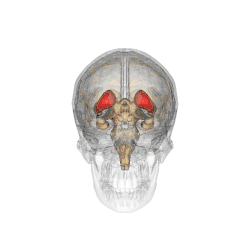

Caudate nucleus

![]() Caudate nucleus (in red) shown within the brain | |